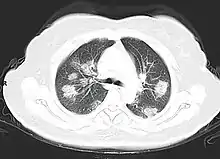

Imaging

Chest CT scans may be helpful to diagnose COVID‑19 in individuals with a high clinical suspicion of infection but are not recommended for routine screening.[163][175] Bilateral multilobar ground-glass opacities with a peripheral, asymmetric, and posterior distribution are common in early infection.[163][176] Subpleural dominance, crazy paving (lobular septal thickening with variable alveolar filling), and consolidation may appear as the disease progresses.[163][177] Characteristic imaging features on chest radiographs and computed tomography (CT) of people who are symptomatic include asymmetric peripheral ground-glass opacities without pleural effusions.[178]

Many groups have created COVID‑19 datasets that include imagery such as the Italian Radiological Society which has compiled an international online database of imaging findings for confirmed cases.[179] Due to overlap with other infections such as adenovirus, imaging without confirmation by rRT-PCR is of limited specificity in identifying COVID‑19.[178] A large study in China compared chest CT results to PCR and demonstrated that though imaging is less specific for the infection, it is faster and more sensitive.[162]